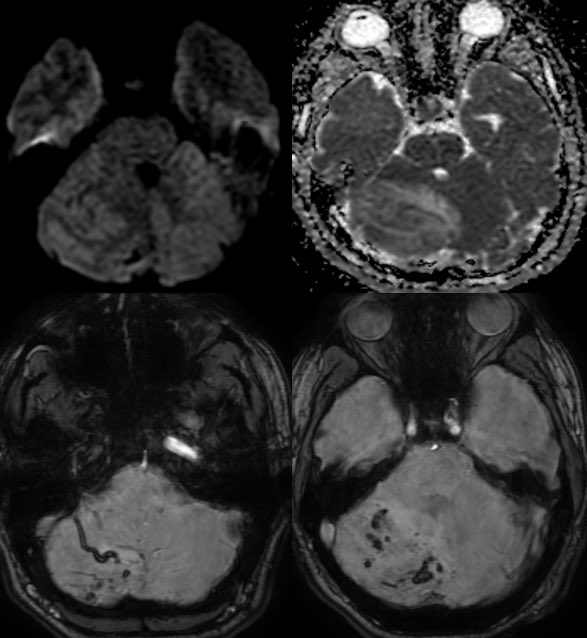

▶️DWI: No diffusion restriction

▶️SWI: patchy areas of hemorrhage and engorged vessels